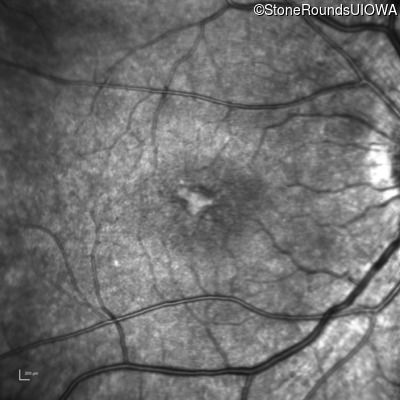

Infrared Fundus Photograph - Right - 20/32 -1

Exemplar